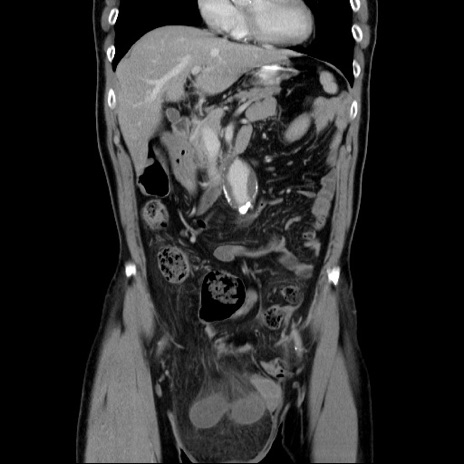

横断像